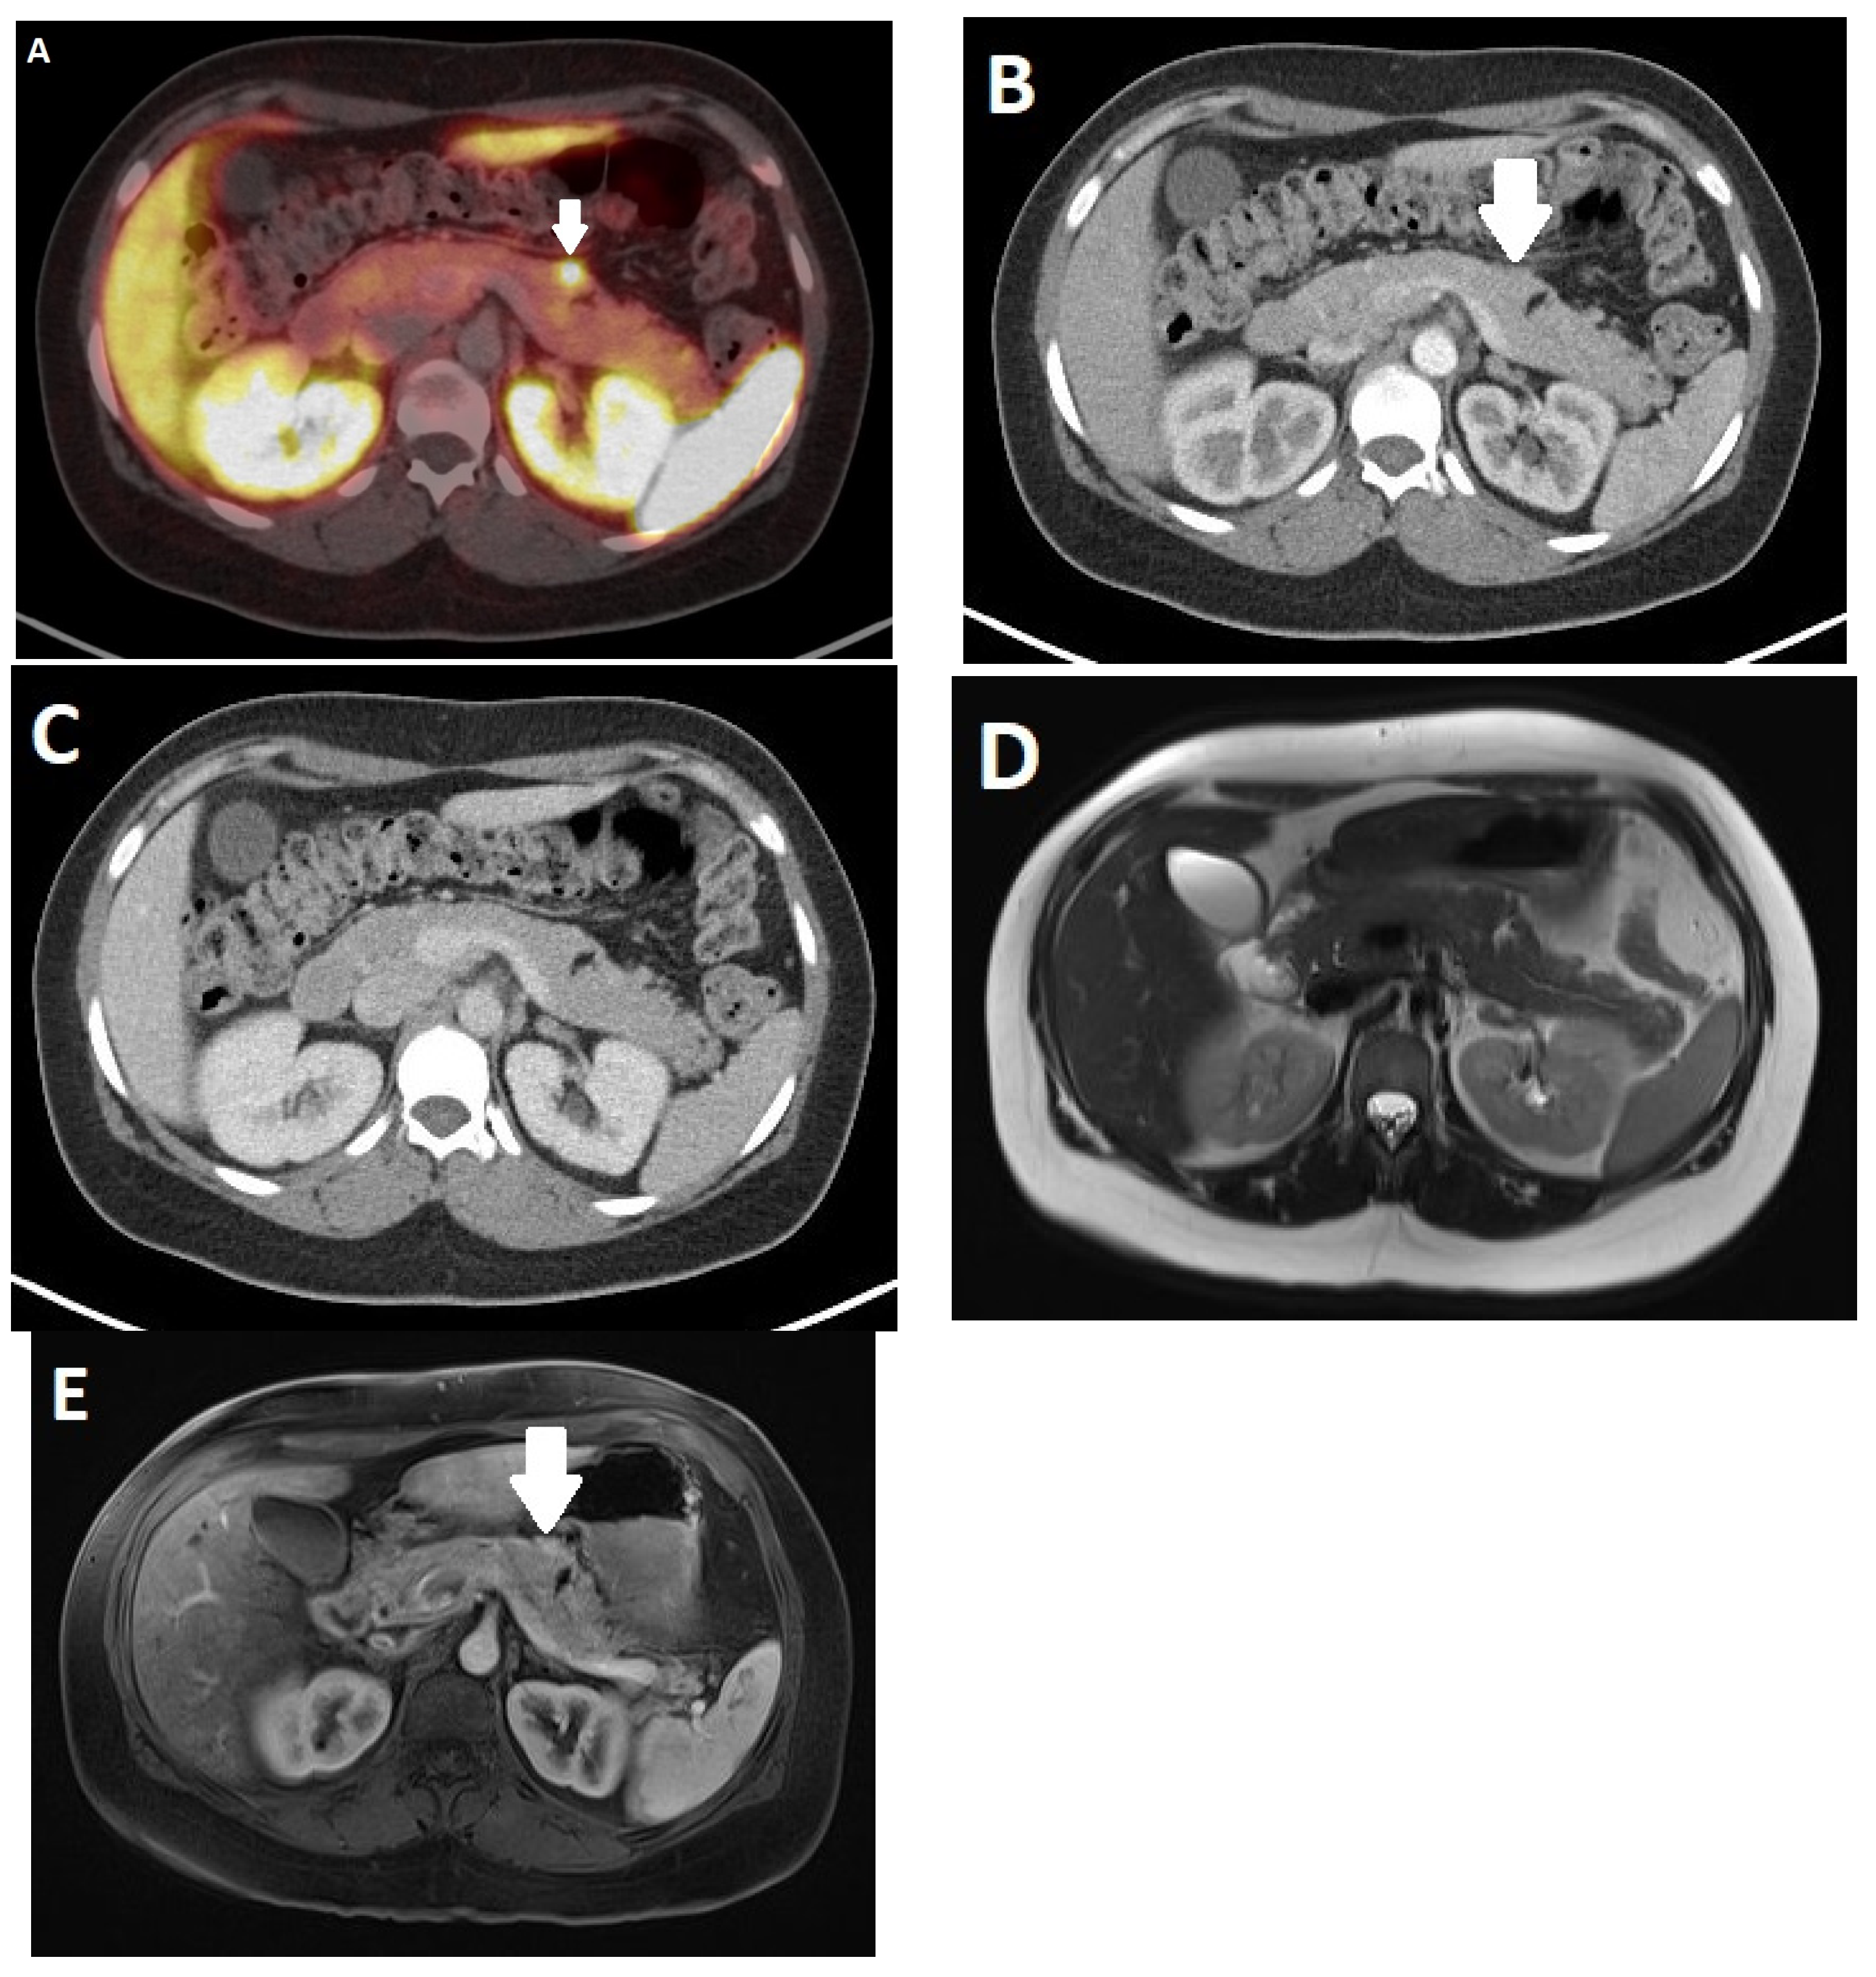

- Yoo, J.; Kim, S.H.; Jeon, S.K.; Bae, J.S.; Han, J.K. Added value of [(68)Ga]Ga-DOTA-TOC PET/CT for characterizing pancreatic neuroendocrine neoplasms: A comparison with contrast-enhanced CT and/or MRI in a large study cohort. Eur. Radiol. 2021, 31, 7734–7745. [Google Scholar] [CrossRef]

- Schmid-Tannwald, C.; Schmid-Tannwald, C.M.; Morelli, J.N.; Neumann, R.; Haug, A.R.; Jansen, N.; Nikolaou, K.; Schramm, N.; Reiser, M.F.; Rist, C. Comparison of abdominal MRI with diffusion-weighted imaging to 68Ga-DOTATATE PET/CT in detection of neuroendocrine tumors of the pancreas. Eur. J. Nucl. Med. Mol. Imaging 2013, 40, 897–907. [Google Scholar] [CrossRef] [PubMed]

- Sadowski, S.M.; Neychev, V.; Millo, C.; Shih, J.; Nilubol, N.; Herscovitch, P.; Pacak, K.; Marx, S.J.; Kebebew, E. Prospective Study of 68Ga-DOTATATE Positron Emission Tomography/Computed Tomography for Detecting Gastro-Entero-Pancreatic Neuroendocrine Tumors and Unknown Primary Sites. J. Clin. Oncol. Off. J. Am. Soc. Clin. Oncol. 2016, 34, 588–596. [Google Scholar] [CrossRef]

- Schraml, C.; Schwenzer, N.F.; Sperling, O.; Aschoff, P.; Lichy, M.P.; Muller, M.; Brendle, C.; Werner, M.K.; Claussen, C.D.; Pfannenberg, C. Staging of neuroendocrine tumours: Comparison of [(6)(8)Ga]DOTATOC multiphase PET/CT and whole-body MRI. Cancer Imaging 2013, 13, 63–72. [Google Scholar] [CrossRef] [PubMed]